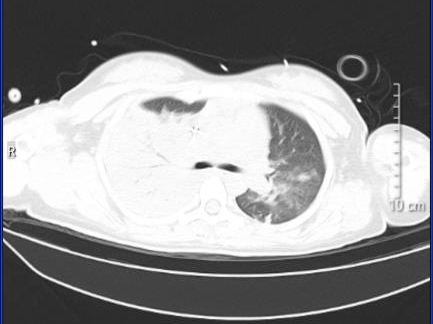

案例2:

58岁阿伯出现咳嗽、咽痛、鼻塞、流涕、头痛,伴有肌肉酸痛,这些症状让阿伯误以为是流感,自行服药后感觉症状加重,甚至出现了呼吸困难。

入院后肺部CT检查结果竟与前几天那名孕妈的如出一辙,同样也是半个肺“全白了”。这让ICU医生警惕起来,迅速考虑到“鹦鹉热”可能,很快便明确了罪魁祸首——“鹦鹉热衣原体”。经过针对性治疗,阿伯的肺部情况明显好转,但由于出现了肝、肾、心等多器官功能损伤,阿伯仍需在ICU接受治疗。

图片

治疗前

治疗后